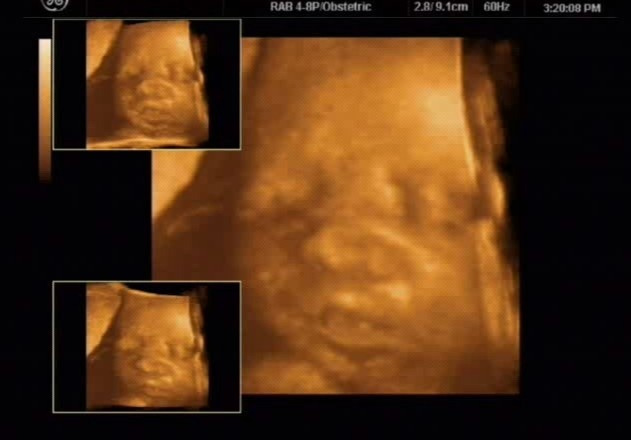

경태 엄마가 가지고 온 입체 초음파 사진 두 장은 태아가 엄마의 마음을 즉각적으로 감지한다는 것을 증명해 준다. ( 경태는 아기의 태명이다. )

하루는 경태 엄마가 병원으로 산전 진찰을 갔다. 긴 시간이 지나도록 호출을 하지 않아 간호사들에게 이유를 물었다. 병원의 실수로 예약자 명단에 빠진 것을 알게 되었다. 해결을 하는 과정에서 경태 엄마는 화가 났다. 병원 관계자들의 사과로 문제는 해결되었으니 이미 시간은 많이 지나간 후였다. 입체 초음파실로에 들어가 침대에 몸을 뉘이고 심호흡을 했지만 계속 속이 상했다. 화면을 보자 경태가 보였다. 초음파를 보던 선생님이 놀라며 말했다. “아기 좀 보세요. 얼른 화 푸셔야겠네요. 경태도 엄마처럼 찡그리고 있잖아요.”화면 안에는 미간을 찡그리고 갈 지자 모양을 하고 있는 입이 보였다. 누가 봐도 화가 난 얼굴이다. 소름이 돋았다. 나의 마음과 경태의 마음이 같았구나.

순간 진정으로 미안한 마음이 들었다. 미안하다는 말을 계속 했다. 5분 가량 지나자 화면 속 경태의 얼굴이 펴졌다. 내려간 입 꼬리와 미간의 주름이 없어진 것이다. 입가에는 옅은 미소마저 보이는 것이 아닌가! 남은 임신기간 동안에는 되도록이면 화를 내지 않겠다고 다짐을 했다.

경태는 잘 태어나 벌써 중학생이 되었다. 지금까지 그사진은 보물처럼 간직하고 있다. 어디를 가던 출산교육 자료로는 최고이기 때문이다. 세상의 어떤 말보다 경태 사진 두 장이면 태교는 끝이 난다.